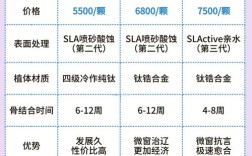

种植系统与材料:

(图片来源网络,侵删)

(图片来源网络,侵删)- 种植体品牌: 提供哪些主流国际知名品牌?(如瑞士的Straumann(士卓曼)、瑞典的Nobel Biocare(诺贝尔)、德国的Ankylos(安格斯)、美国的Zimmer(捷迈)、韩国的Osstem(奥齿泰)、Dentium(登腾)等),不同品牌在技术、设计、临床数据、长期成功率、价格上有所差异,了解医生推荐的品牌及其理由。

- 牙冠材料: 提供哪些牙冠选择?(如全瓷冠、烤瓷冠等),全瓷冠美观、生物相容性好,是目前的主流选择。

- 材料来源: 是否使用正规渠道来源的、有明确标识和保质期的产品?要求查看产品包装和说明书。

- 费用构成清晰: 种植牙费用通常包括:种植体费用、基台费用、牙冠费用、手术费、检查费(CBCT等)、麻醉费等,要求机构提供详细、透明、书面的报价单,列明每一项费用。